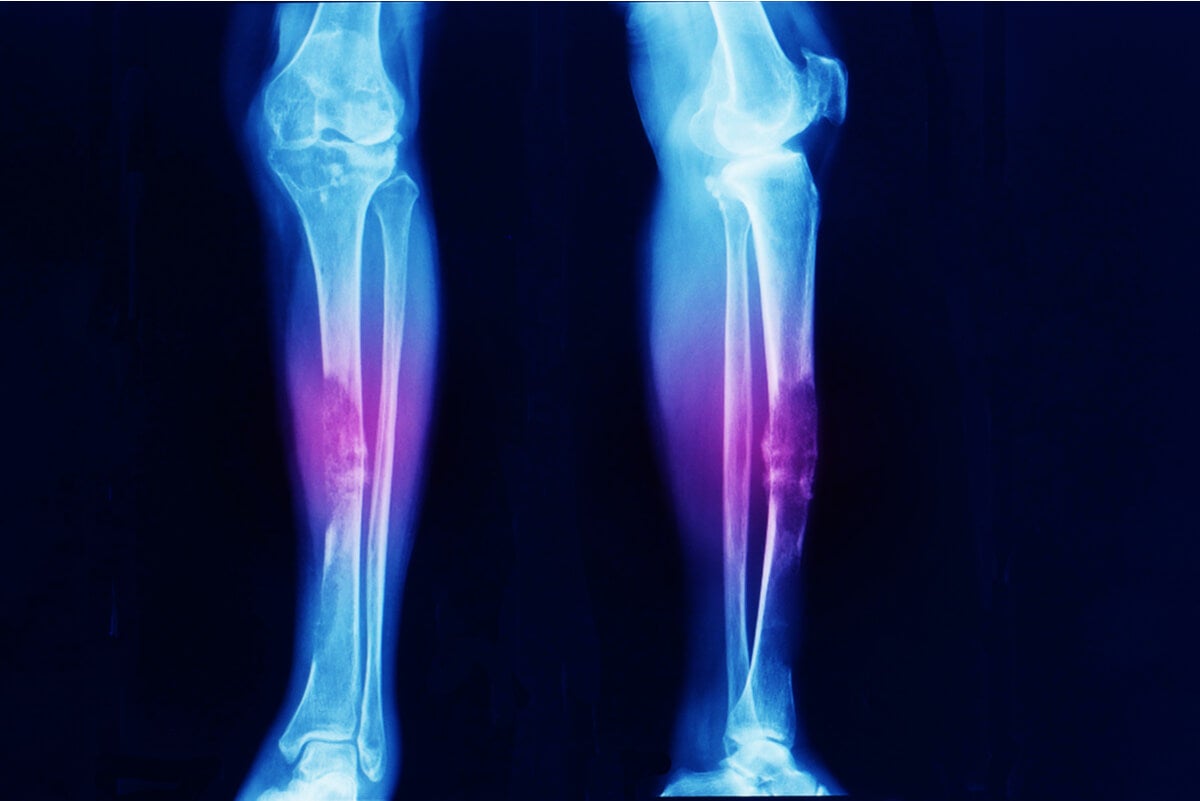

que es un sarcoma abdominal Un sarcoma es un tumor maligno raro, que se desarrolla en el tejido conjuntivo, tejido de conexión de los órganos y evoluciona rápidamente por todo el organismo. El primer signo de un sarcoma en un brazo, una pierna o el tronco puede ser un bulto o hinchazón sin dolor. El sarcoma de tejido blando es una enfermedad por la que se forman células malignas (cancerosas) en los tejidos blandos del cuerpo. El sarcoma de tejido blando es un tipo de cáncer poco frecuente que comienza en los tejidos que conectan, sostienen y recubren otras estructuras del. El liposarcoma puede producirse en las células grasas de cualquier parte del cuerpo, pero,. El rabdomiosarcoma (rms) es un tipo raro de cáncer que se forma en el tejido blando, específicamente en el tejido muscular del esqueleto o, a veces, en. Es posible que ciertos trastornos. Se conoce como sarcoma a un grupo de cánceres cuyo origen se encuentra en las células del tejido conjuntivo, el cual conforma la estructura del cuerpo humano.